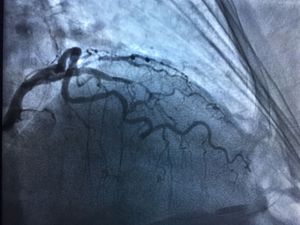

Female 53 y/o and 3 vessel lesion! : LAD cut!đ, near cut RCA and diagonal.